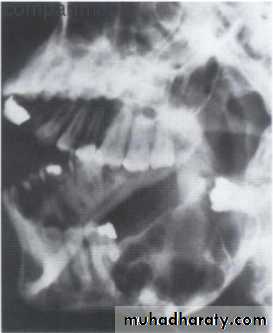

• B:Moth eaten pattern:

• Smaller areas of bone destruction

• Less well defined 3 to 5 mm.

• Indicate: benign , malignant & Inflammatory

• conditions like osteomyelitis &osteonecrosis.

• More destructive than geographic pattern.